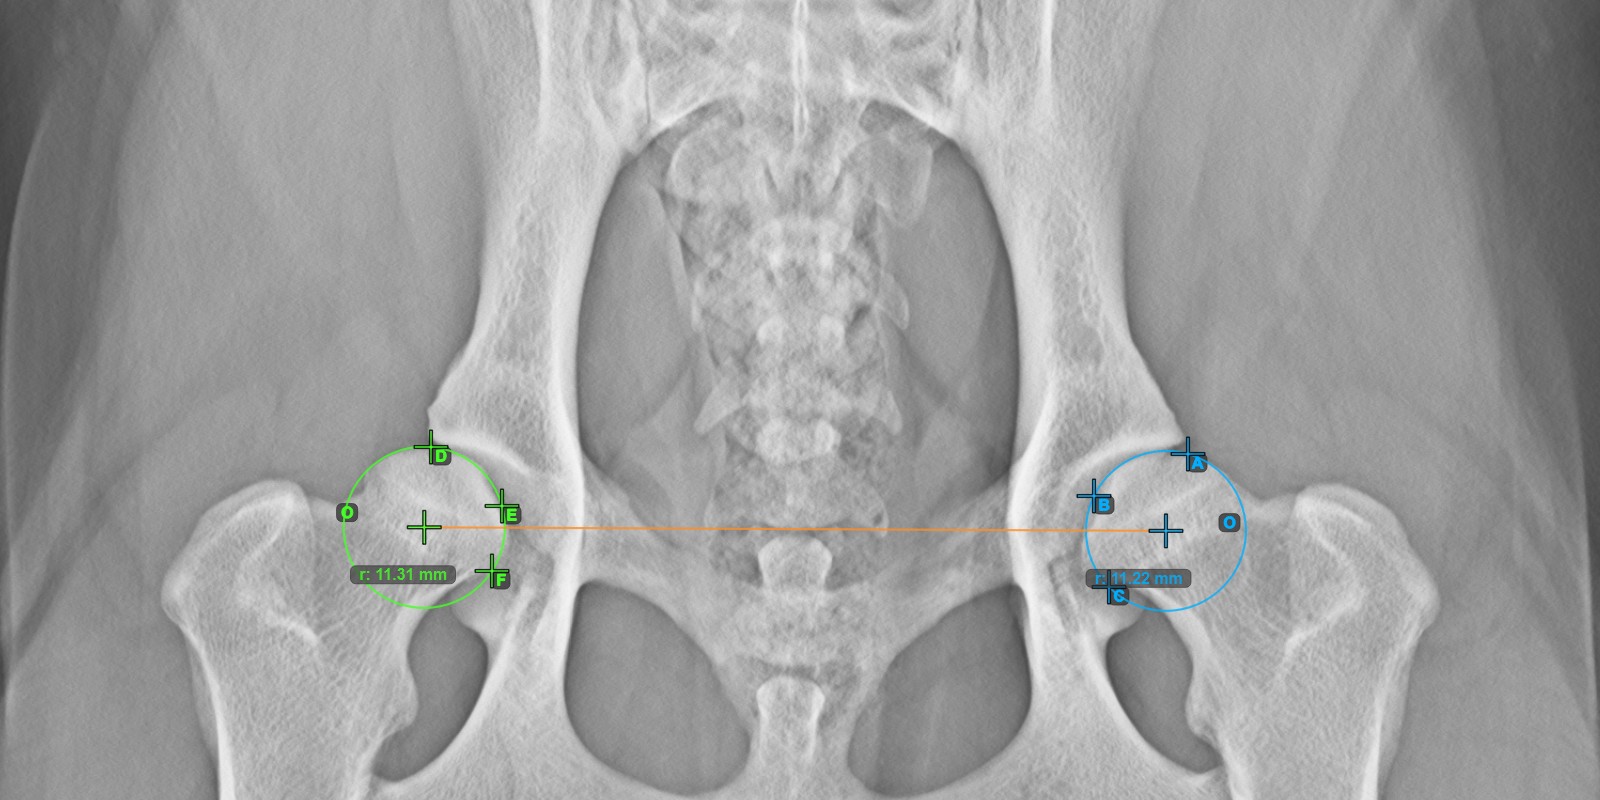

A lenti kép az **bal* Caput Femoris ízületi felszínén elhelyezett három pont tipikus elhelyezkedését ábrázolja.*

Folytassa a mérést a három pont megjelölésével a jobb Caput Femoris ízületi felszínén.

Jelölje meg a három pontot a jobb Caput Femoris ízületi felszínén (a Fovea Capitilis kívül). A sorrendtől függetlenül ügyeljen arra, hogy megjelölje a legfelső pontot, a legalacsonyabb pontot és a combfej középpontját. A három pont alapján a rendszer automatikusan létrehoz egy kört.

A két kör origói automatikusan összekapcsolódnak egy vonallal, amely meghatározza az építendő szögek kezdeti oldalát.

A lenti kép a **jobb* Caput Femoris ízületi felszínén elhelyezett három pont tipikus elhelyezkedését ábrázolja.*